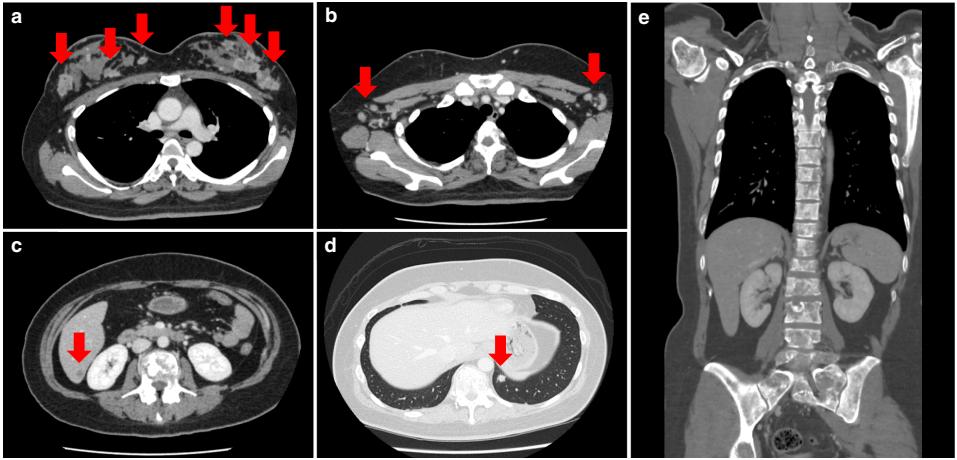

血液检测提示肝功能不全和血清钙升高。骨吸收指标高。由于患者不明原因的肝功能不全,决定做全身CT检查。显示双侧乳房多发性增强肿块,多发性淋巴结转移,脊柱多发性骨转移,肺转移和肝转移(图2)。怀疑是晚期乳腺癌。双侧乳腺组织穿刺活检显示浸润性HER2阳性导管癌(图3)。腰痛是由乳腺癌脊柱转移导致的压缩性骨折所引起。患者在产后8个月开始用紫杉醇和曲妥珠单抗进行化疗。治疗两年半后,临床病情完全缓解。

图2. 增强CT图像。a双侧乳房出现对比增强肿块(箭头);b转移至双侧腋窝淋巴结(箭头);c肝S7区转移(箭头);d左肺下叶转移(箭头);e所有可见的椎体都有转移